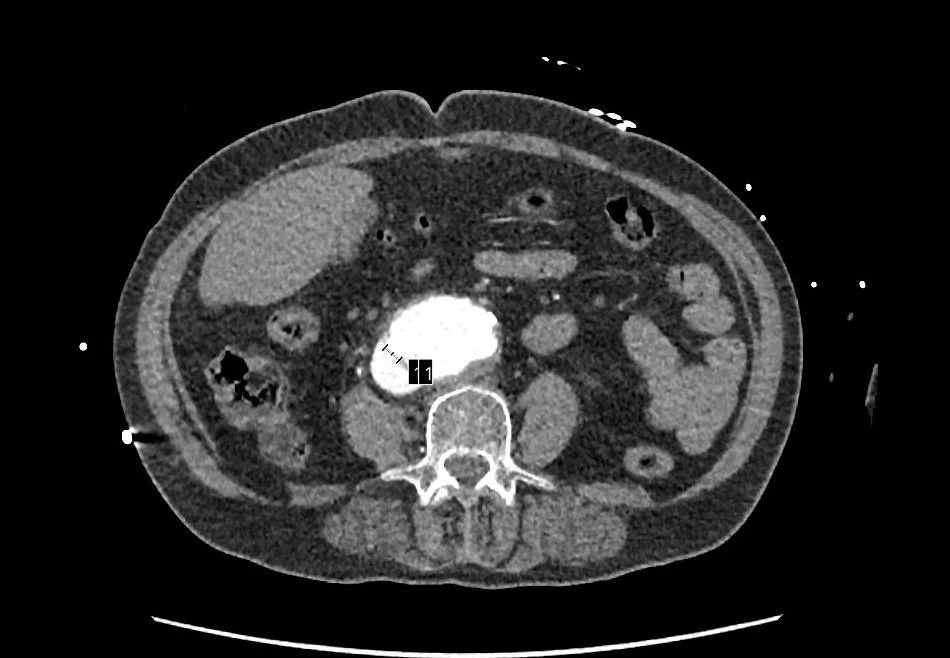

Sheperdigian says a consult and surgery with Franco Rea, MD, saved her life. The culprit, illuminated by the CT Sheperdigian ordered and shown below: an aortocaval fistula.

‍An ACF is a rare, life-threatening complication in which an abdominal aortic aneurysm erodes into the adjacent inferior vena cava, causing a direct, high-pressure shunt between the two vessels. Immediate surgery is required, as untreated cases have a near 100-percent mortality rate, according to NIH.